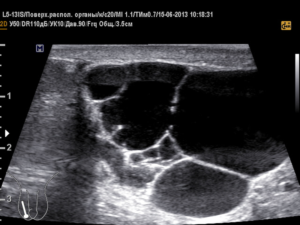

Варикоцеле

Необходимость своевременного лечения варикозного расширения вен семенного канатика обусловлена вероятностью развития бесплодия у мужчины.

На УЗИ при варикоцеле четко визуализируются расширенные видоизмененные вены, диаметр которых больше 3 мм.

Как известно, существует 3 стадии варикозной болезни. При первой визуализация вен происходит при повышении внутрибрюшного давления либо при диагностики в вертикальном положении, во второй — видоизмененные вены не исчезают и в горизонтальном положении пациента, в 3 стадии вены просматриваются ниже полюса уменьшенного в размерах яичка.